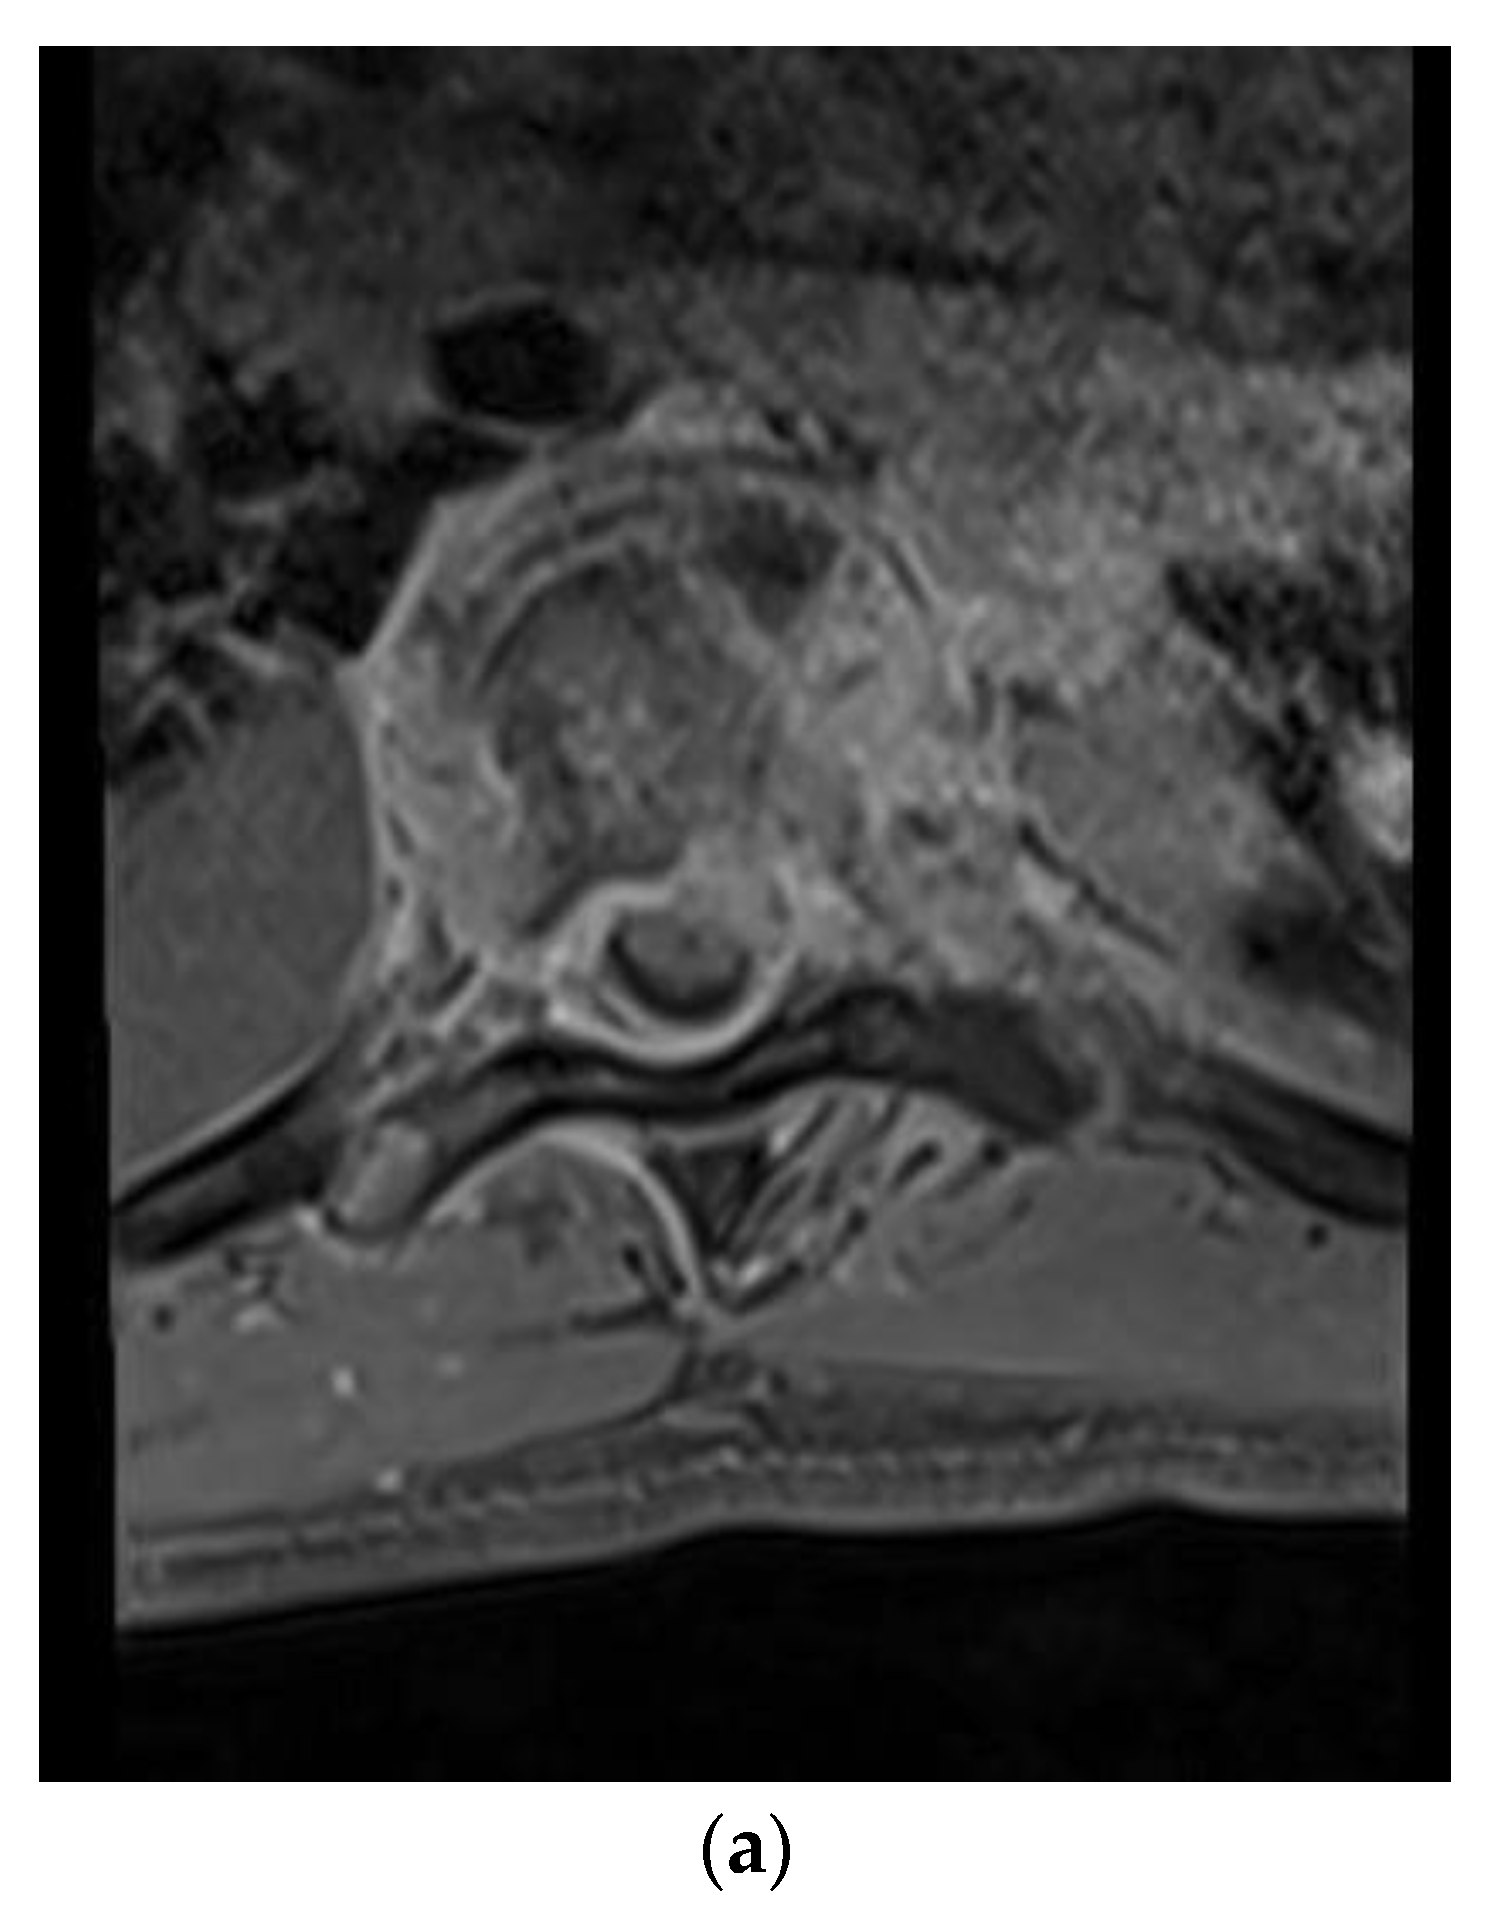

A 28-year-old man presented with a one-month history of lower back pain, worsening shortness of breath, and intermittent fevers over a period of the month. He was initially treated with azithromycin at an outside facility, which failed to resolve his symptoms. The back pain was progressively severe and radiated to both lower extremities, limiting his ambulation. He had no history of sick contacts, travel, or history of exposure to tuberculosis patients. Initial treatment included empiric antibiotics and screening tests for HIV, tuberculosis with PCR, legionella, and a endemic mycosis serology panel that included histoplasmosis, blastomycosis, and coccidioidomycosis. A CT scan of the chest revealed lucencies throughout mid-thoracic spine with adjacent prominence of paraspinal soft tissues suggestive of osteomyelitis and discitis. MRI of the T spine revealed abnormal marrow enhancement seen with varying degrees of paraspinal soft tissue enhancement, the most significant being at T6 where diffuse marrow enhancement and vertebral height loss was seen (Figure 1a,b). A biopsy of the lesion confirmed the coccidioidomycosis (Figure 1c). He was initiated on antifungal therapy—voriconazole and amphotericin B—followed by surgical debridement and stabilization.

Figure 1. (a) Axial T1-weighted magnetic resonance (MR) images with contrast showing extensive vertebral body and soft tissue enhancement with compression of the spinal canal at T6. (b) Sagittal T1-weighted MR Images with contrast showing extensive enhancement throughout the vertebral bodies and soft tissue but most significantly at T6–7. (c) Hematoxylin and eosin (H&E) staining of the thoracic bone specimen showing acute osteomyelitis with abundant coccidioides organisms. Multinucleated giant cells with engulfed coccidioides spherules is a characteristic finding. Abundant acute inflammatory changes was noted in the marrow cavity.